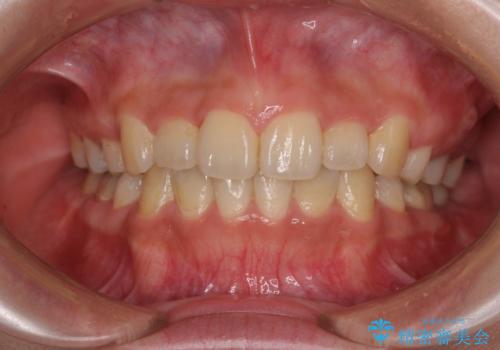

- 上顎の八重歯と前歯のデコボコを気にして来院された患者様です。

八重歯の移動量が多く、インビザライン単体での治療は困難と判断し、補助装置により八重歯移動後にインビザラインを用いることとしました。

治療途中で遠方に転勤となったため、通院が困難となり治療期間が長期化してしまいました。

上顎のみの抜歯矯正をインビザラインで行う場合、奥歯の前方移動がインビザラインでは苦手のため、奥歯の咬み合わせが不十分となることがあります。

今回の治療では終了時に奥歯は接触しているものの、接触の程度は物足りないものがある状態でした。今後保定期間に少しずつ奥歯の咬合を改善させていくことになります。